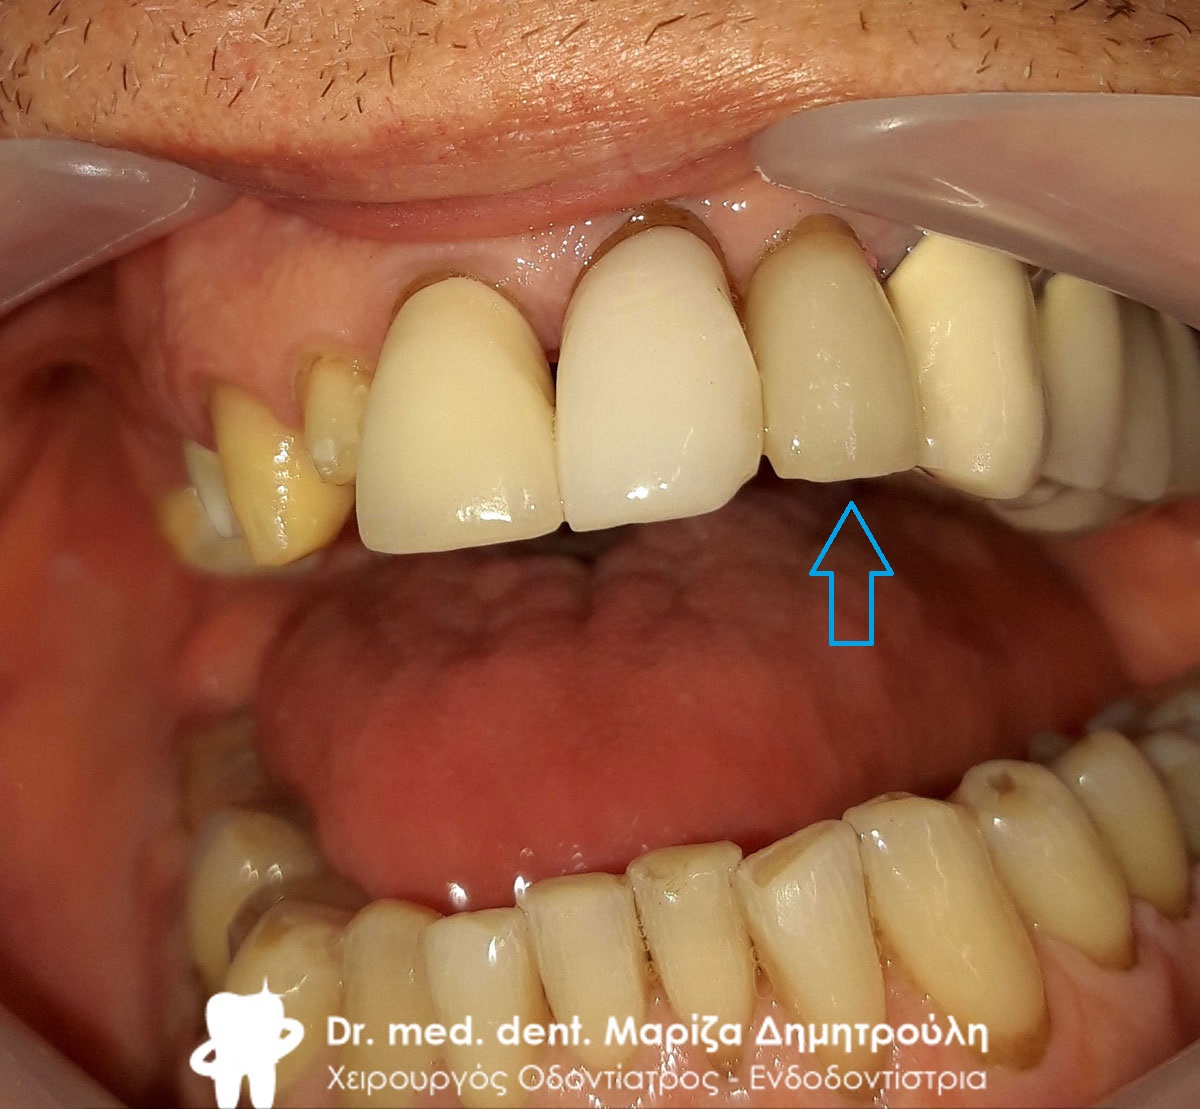

Τελική εικόνα του ολοκεραμικού πέταλου ζιρκονίου στην κάτω γνάθο

Τελική εικόνα του ολοκεραμικού πέταλου ζιρκονίου στην κάτω γνάθο

Τελική κλινική εικόνα του στόματος του ασθενή

Τελική εικόνα της ολοκεραμικής γέφυρας ζιρκονίου στην κάτω γνάθο

Τελική εικόνα της ολοκεραμικής γέφυρας ζιρκονίου στην κάτω γνάθο

Τελική εικόνα της ολοκεραμικής γέφυρας ζιρκονίου

Τελική εικόνα της ολοκεραμικής γέφυρας ζιρκονίου

Τελική εικόνα της ολοκεραμικής γέφυρας ζιρκονίου

Τελική εικόνα της ολοκεραμικής γέφυρας ζιρκονίου

Τελική εικόνα της ολοκεραμικής γέφυρας ζιρκονίου